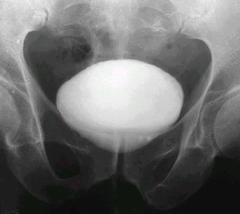

老人得了膀胱結石的癥狀

老人得了膀胱結石的癥狀?老年人年紀一大,身體素質也就會下降不少,很多疾病也就找上門了,今天要跟大家介紹的就是比較多見的膀胱結石,下面來了解下膀胱結石都有什么癥狀吧。

齊齊哈爾?現代專家說,膀胱結石的具體癥狀表現有以下幾種:

一、排尿困難:典型的膀胱結石的癥狀是患者在排尿時尿流突然中斷和陰莖頭部劇痛,這是由于結石突然嵌頓在尿道內口引起膀胱括約肌的痙攣所致。當患者變換體位而使結石移動時,又可排尿而劇痛得以緩解。出現膀胱結石的癥狀后,患者為避免排尿時發(fā)生劇烈疼痛,常呈特殊排尿體位,即站立排尿時雙膝前屈,軀干部后仰約30度,排尿時小心翼翼,如有尿線變細或中斷,再適當變動體位使結石移動后再行排尿。有的患者可有排砂石的病史。

二、疼痛:膀胱結石的癥狀中的疼痛可為下腹部和會陰區(qū)鈍痛,也可為明顯疼痛,常因活動而誘發(fā)或加劇。

三、膀胱刺激:膀胱結石合并感染時,出現膀胱刺激癥狀、血尿和膿尿。膀胱結石由于對膀胱局部的刺激、梗阻和繼發(fā)感染,可產生各種膀胱結石的癥狀。結石引起的膀胱刺激、繼發(fā)慢性炎性反應可引起膀胱鱗狀上皮癌等比較嚴重的并發(fā)癥,所以膀胱結石應早治療,必須高度重視。

四、結石刺激膀胱黏膜時,膀胱結石的癥狀可有尿頻、尿急、尿痛,排尿終末時疼痛加劇,且可伴有終末血尿。患者常改變體位如臥位以求疼痛緩解。

以上就是關于“老人得了膀胱結石的癥狀?”的全部內容了,希望會對老年朋友們有所幫助。專家提醒,膀胱結石危害很大,一旦患上了這一疾病,要積極的治療這一疾病,不要等到危害出現了才后悔。祝大家健康。